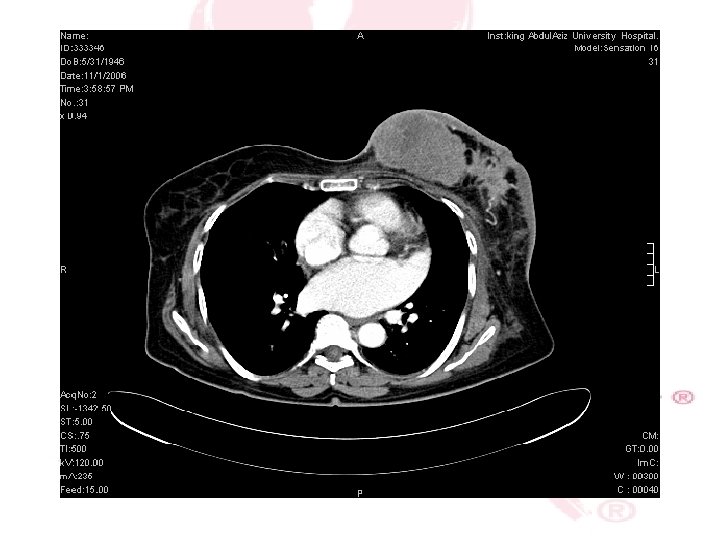

CT SCAN CHEST , ABDOMEN &PELVIS